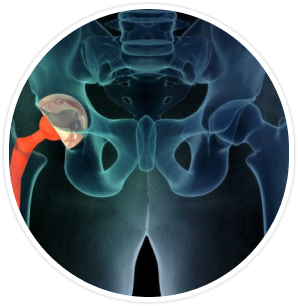

Restore mobility and comfort with our advanced Bikini Hip Replacement procedure at The Hip Surgeon

Bikini Hip Replacement in Indore is a minimally invasive surgical procedure that aims to improve mobility and relieve pain in the hip joint. This innovative technique allows for smaller incisions typically made along the bikini line, resulting in a more cosmetically pleasing outcome for patients.

One of the key benefits of MIS Hip Replacement is the lower risk of dislocation post-surgery. The precise nature of the bikini anterior hip replacement technique helps to stabilize the hip joint, reducing the chances of complications.

A small bikini incision will be made for MIS hip replacement surgery to access the hip joint.

Surgeon will carefully expose the hip joint during the bikini hip replacement procedure.